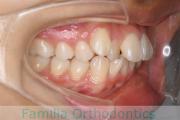

八重歯を治したいということで来院されました。下あごの左ずれのある上顎前突(出っ歯)・叢生(でこぼこ)でしたので、上は左右から、下はで左のみ小臼歯を抜歯して、歯科矯正用アンカースクリューとマルチブラケット法にて治療を行いました。2年強、30回程度の通院が必要でした。

上下とも前歯の叢生(でこぼこ、凹凸、ガタガタ)があるため、保定を怠ると後戻りのリスクがあります。